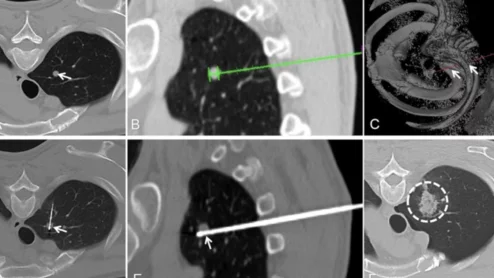

Robotic-assisted RFAs yield better outcomes during lung tumor ablations

Often integrated with artificial intelligence, these systems have been shown to improve accuracy and reproducibility during IR care.